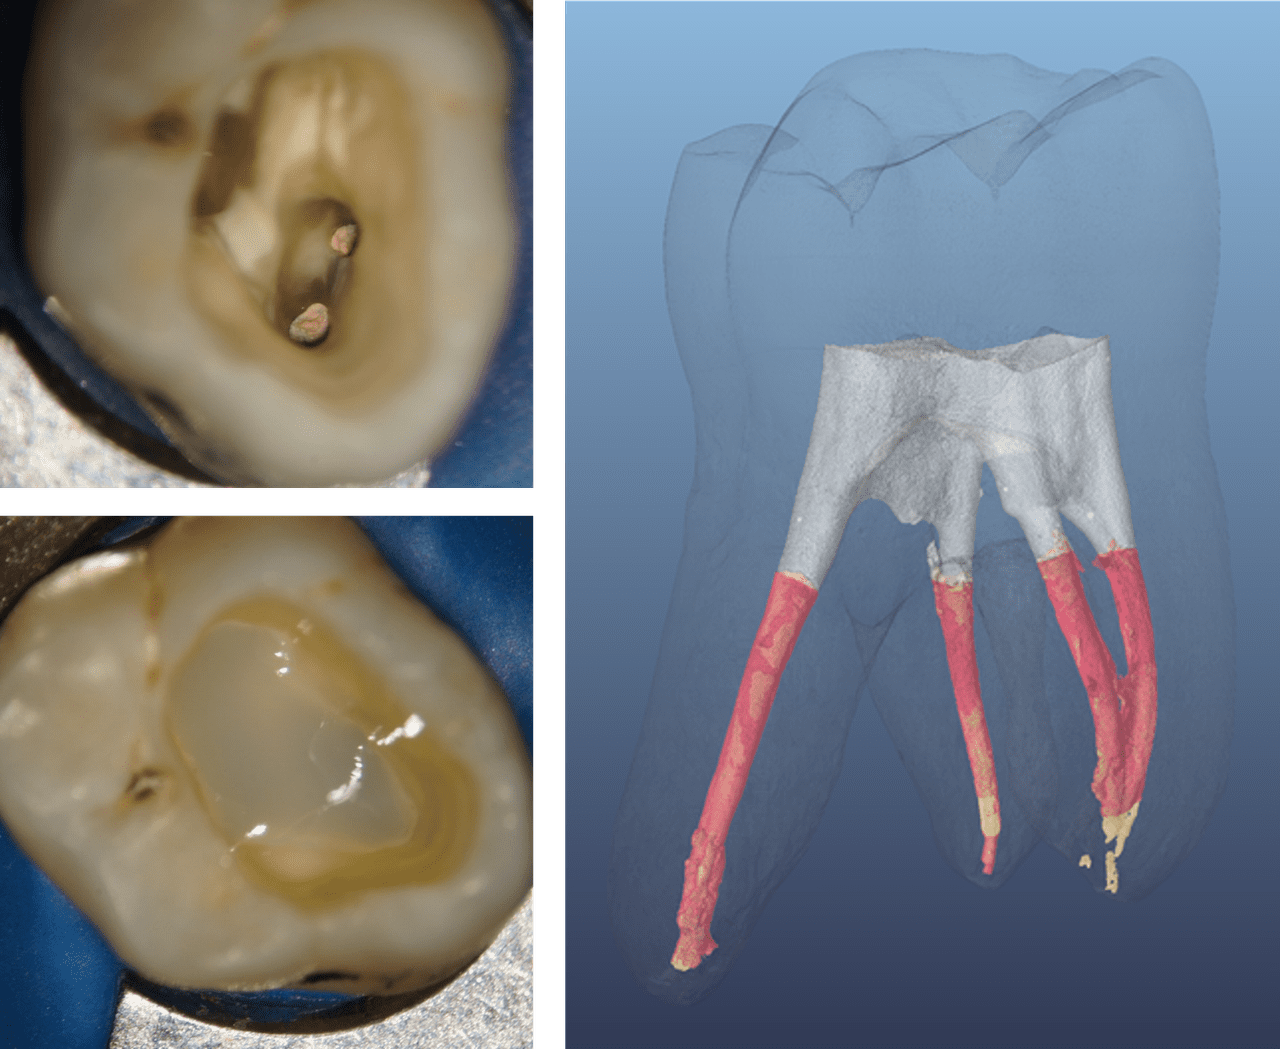

Figure 2: Endodontically treated posterior teeth with four and three coronal walls, and barely undermined residual tooth structure before and after direct restoration

(Courtesy of Dr. Marcus Holzmeier, Germany)